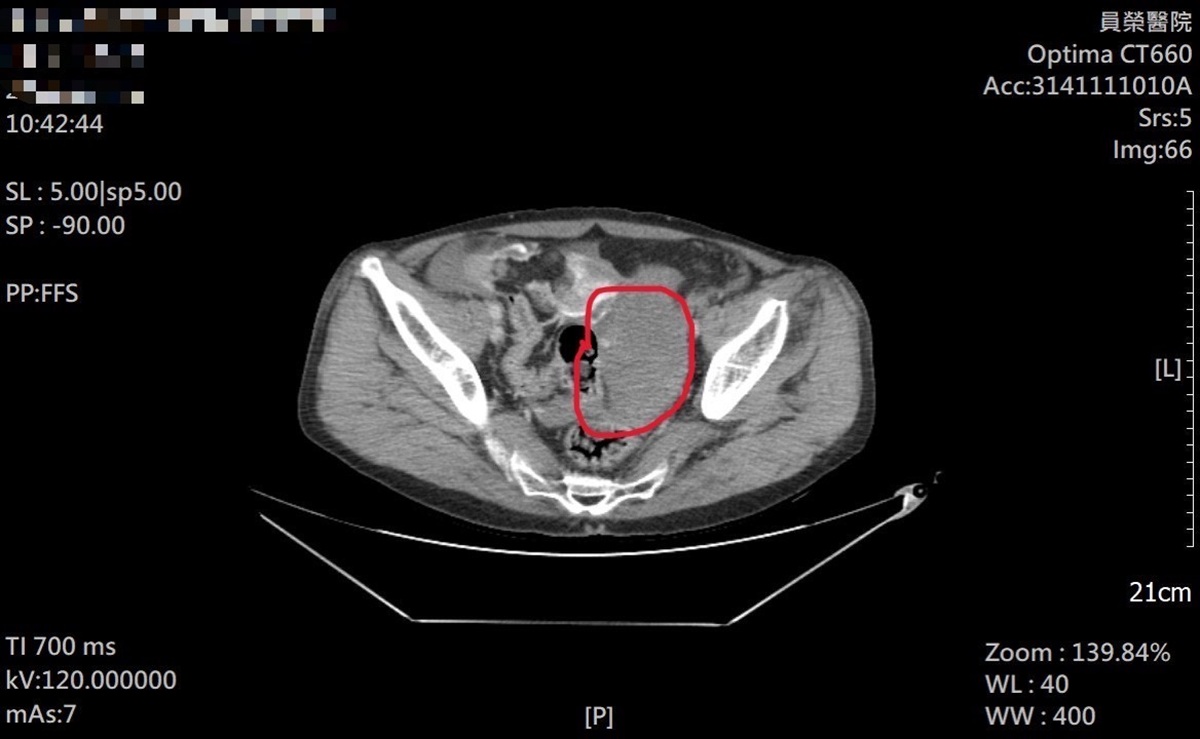

急診團隊立即為患者施予止痛處置並安排抽血、X光與電腦斷層檢查。雖然四肢與頭部影像未見明顯骨折線,但CTA影像顯示疑似腸系膜出血。王醫師評估患者年齡及既往心血管病史(含搭心臟支架、肺部手術及慢性吸菸史)等高風險因素,啟動緊急轉診。

▲王醫師呼籲,看似外傷表淺,仍可能伴隨深層肌肉出血、腸系膜破裂、骨盆損傷或內臟挫傷,延誤治療恐影響生命安全。(圖/員榮醫院提供)